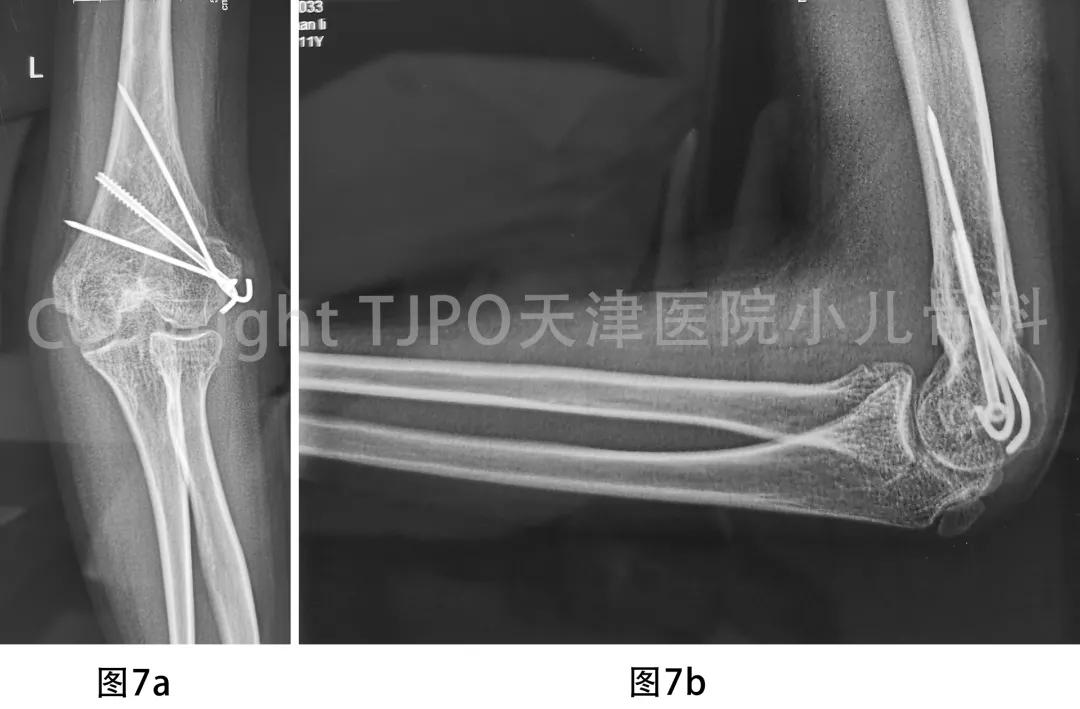

术后早期开始指导下功能康复训练,术后4个月复查示截骨端愈合良好,拆除外固定架。二次术后1年复查,截骨端愈合良好,功能正常,初次术前轻度尺神经损伤表现已完全恢复(图7)。

7a-图7b 二次术后1年X线片示肱骨髁上截骨端愈合良好,外观及功能恢复